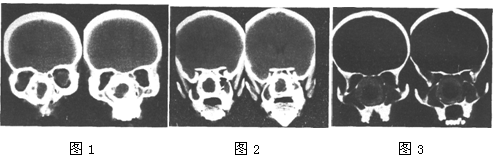

[单选题]女,14岁,渐进性鼻塞2年余,右眼肿痛数月,CT如图所示,最可能的诊断是()A . 筛骨骨肉瘤B . 筛骨骨纤维结构不良C . 筛骨软骨瘤D . 筛骨结核E . 筛骨骨化性纤维瘤